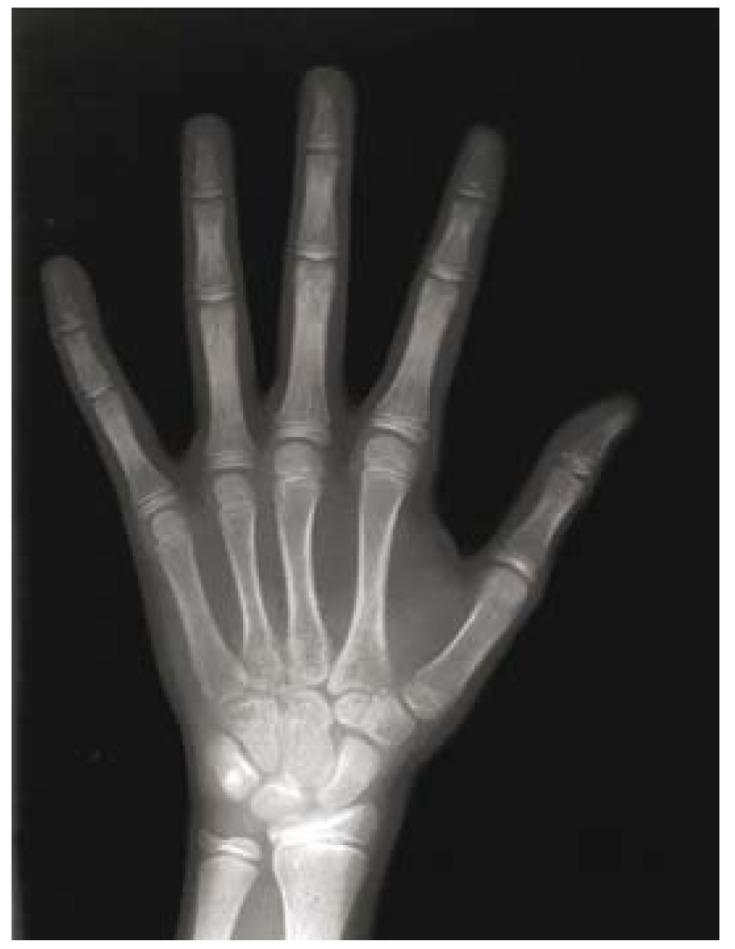

In this study, a total of 52 patients (26 males and 26 females), referring to Mashhad School of Dentistry for orthodontic treatment, were evaluated; the subjects were within the age range of 9-14 years. Hand-wrist radiographic evaluation of skeletal maturation was performed using Fishman method. Also, the Demirjian method was used to identify the stages of dental calcification by panoramic radiographs. Independent t-test and Spearman correlation coefficient were used for data analyses.

本研究共评估了52例转诊至马什哈德牙科学院接受正畸治疗的患者(26例男性和26例女性);受试者年龄在9至14岁之间。采用菲什曼法对手腕部进行骨骼成熟度的X线摄影评估。此外,使用德米尔坚法通过全景X线片确定牙齿钙化阶段。数据分析采用独立t检验和斯皮尔曼相关系数。